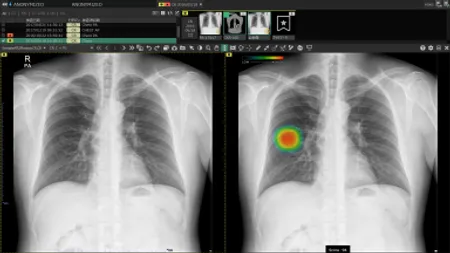

本製品は胸部単純X線写真の読影の際に医師に診断補助となる情報を提供するAIです。

胸部単純X線画像を自動解析。結節・腫瘤影、浸潤影、気胸が疑われる領域を検出しマーキングします。

AI技術を活用し、医療現場の胸部X線画像診断への 課題を解決したいという思いから生まれた 次世代画像解析技術です。

胸部X線画像における包括的な読影支援を提供